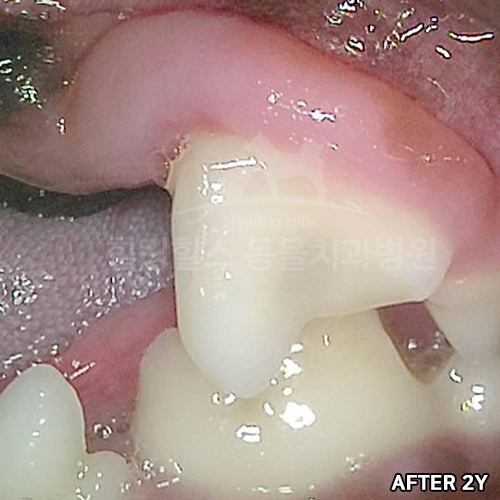

[강아지발치] 잇몸뼈가 녹은 구멍에 자기잇몸뼈가 튼튼하게 재생되어 채워졌어 - 강아지치아발치 2년 후 구강X-ray 비교! -

2025.11.26